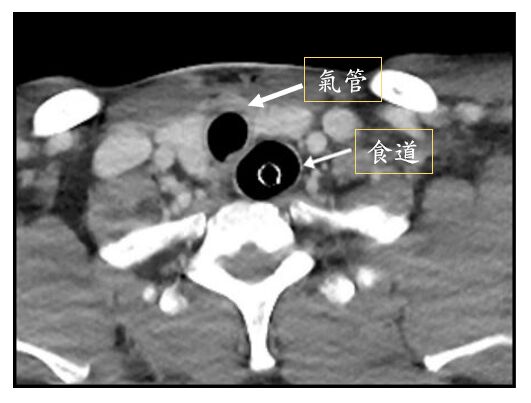

食道(esophagus)在氣管(trachea)的後方,所以考題中前面的洞是氣管、後面是食道。

氣管內管的主要是由塑膠構成,而外圍有一圈圈放射線不可穿過的線(radiopaque line),才可以在CT影像上呈現亮亮的一圈

因此,這題只能選(A) 食道插管(esophageal intubation),氣管內管原本要插到氣管內,但現在不小心插到食道,稱為食道插管